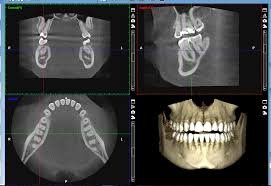

Digital Radiography - Gone are the days of X rays washed in harmful chemicals like Developer and Fixer. Today most Dental X rays are digital. We are proud to have gone digital since 1998. This means less radiation dosage to you compared to the old ch

Digital Radiography

Gone are the days of X rays washed in harmful chemicals like Developer and Fixer. Today most Dental X rays are digital. We are proud to have gone digital since 1998. This means less radiation dosage to you compared to the old chemically processed film.  We take an intra oral X ray and you see it instantly on the screen.